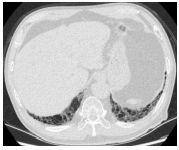

7.CC: cough for one year and back pain